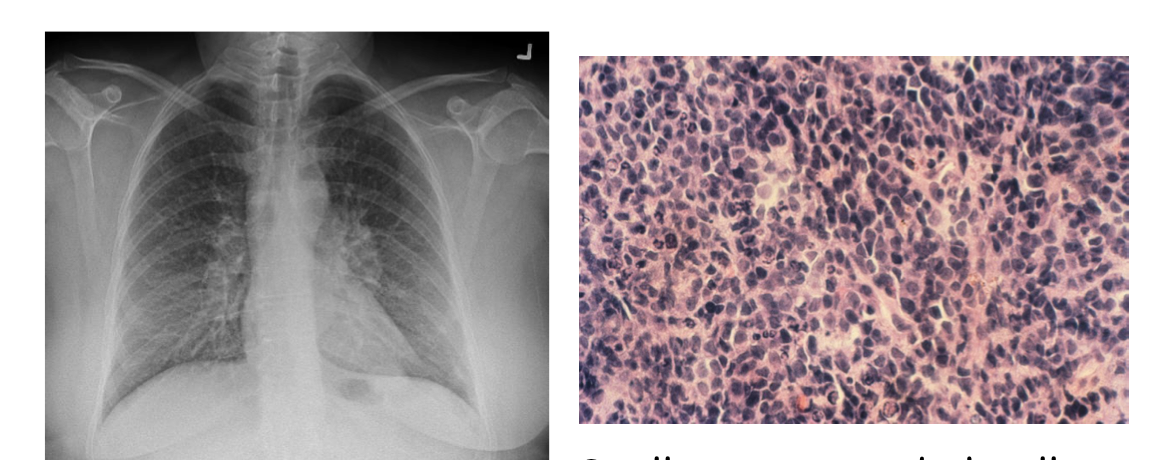

• 60F with small-volume hemoptysis for 2 weeks, has had a

worsened headache for the last week • Profile

• Current 40pack-yr smoker • Current waitress • Meds/Allergies: none

• Vitals normal • ?Left supraclavicular

lymphadenopathy • Resp exam: hyperinflation • Normal CV exam • No abdo organomegaly

• CBC

• Hgb 150 (N Indices), Platelets 285, WBC 9.0 (N Diff)

• Electrolytes/Renal Function

• Na 133, K 4.0, Cl 95, HCO3 28, Creatinine 80 (eGFR 75) • Calcium 2.35

• Liver Function Tests

• ALT 55, Bili 18, Albumin 30

Mild Liver Enzyme Abnormalities

what type of cancer?

Squamous cell carcinoma